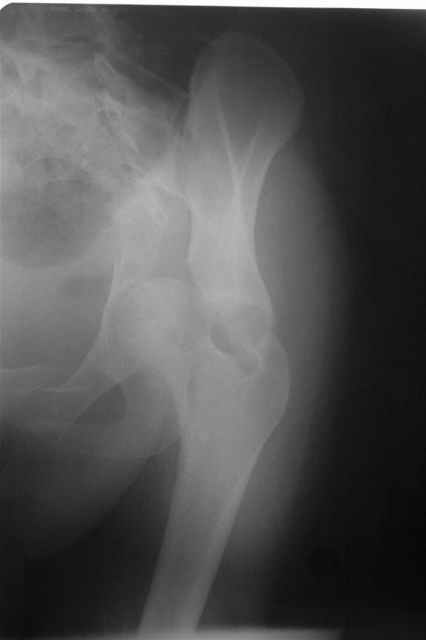

Трудности возникли сразу после рассечения большой ягодичной мыцы - короткие наружные ротаторы едва ли определялись - головка и шейка (как видно на

снимке) ушли в таз, пришлось воспользоваться дистрактором( ручные попытки выдернуть голову из под проксимального фрагмента - безуспешны) Шарнирный дистрактор - великое изобретение, без него репозиция была просто невозможна.

P.S. в приложении R пациентки с похожей проблемой доступа.. за исключением того, что перелом

двухколонный. Вертлугу лечили Y доступом.